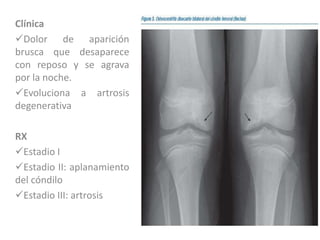

Osteonecrosis del condilo femoral

Afecta el condilo medial

Afecta con más frecuencia a

las mujeres

Mayores de 60 años

Clínica

Dolor de aparición

brusca que desaparece

con reposo y se agrava

por la noche.

Evoluciona a artrosis

degenerativa

RX

Estadio I

Estadio II: aplanamiento

del cóndilo

Estadio III: artrosis